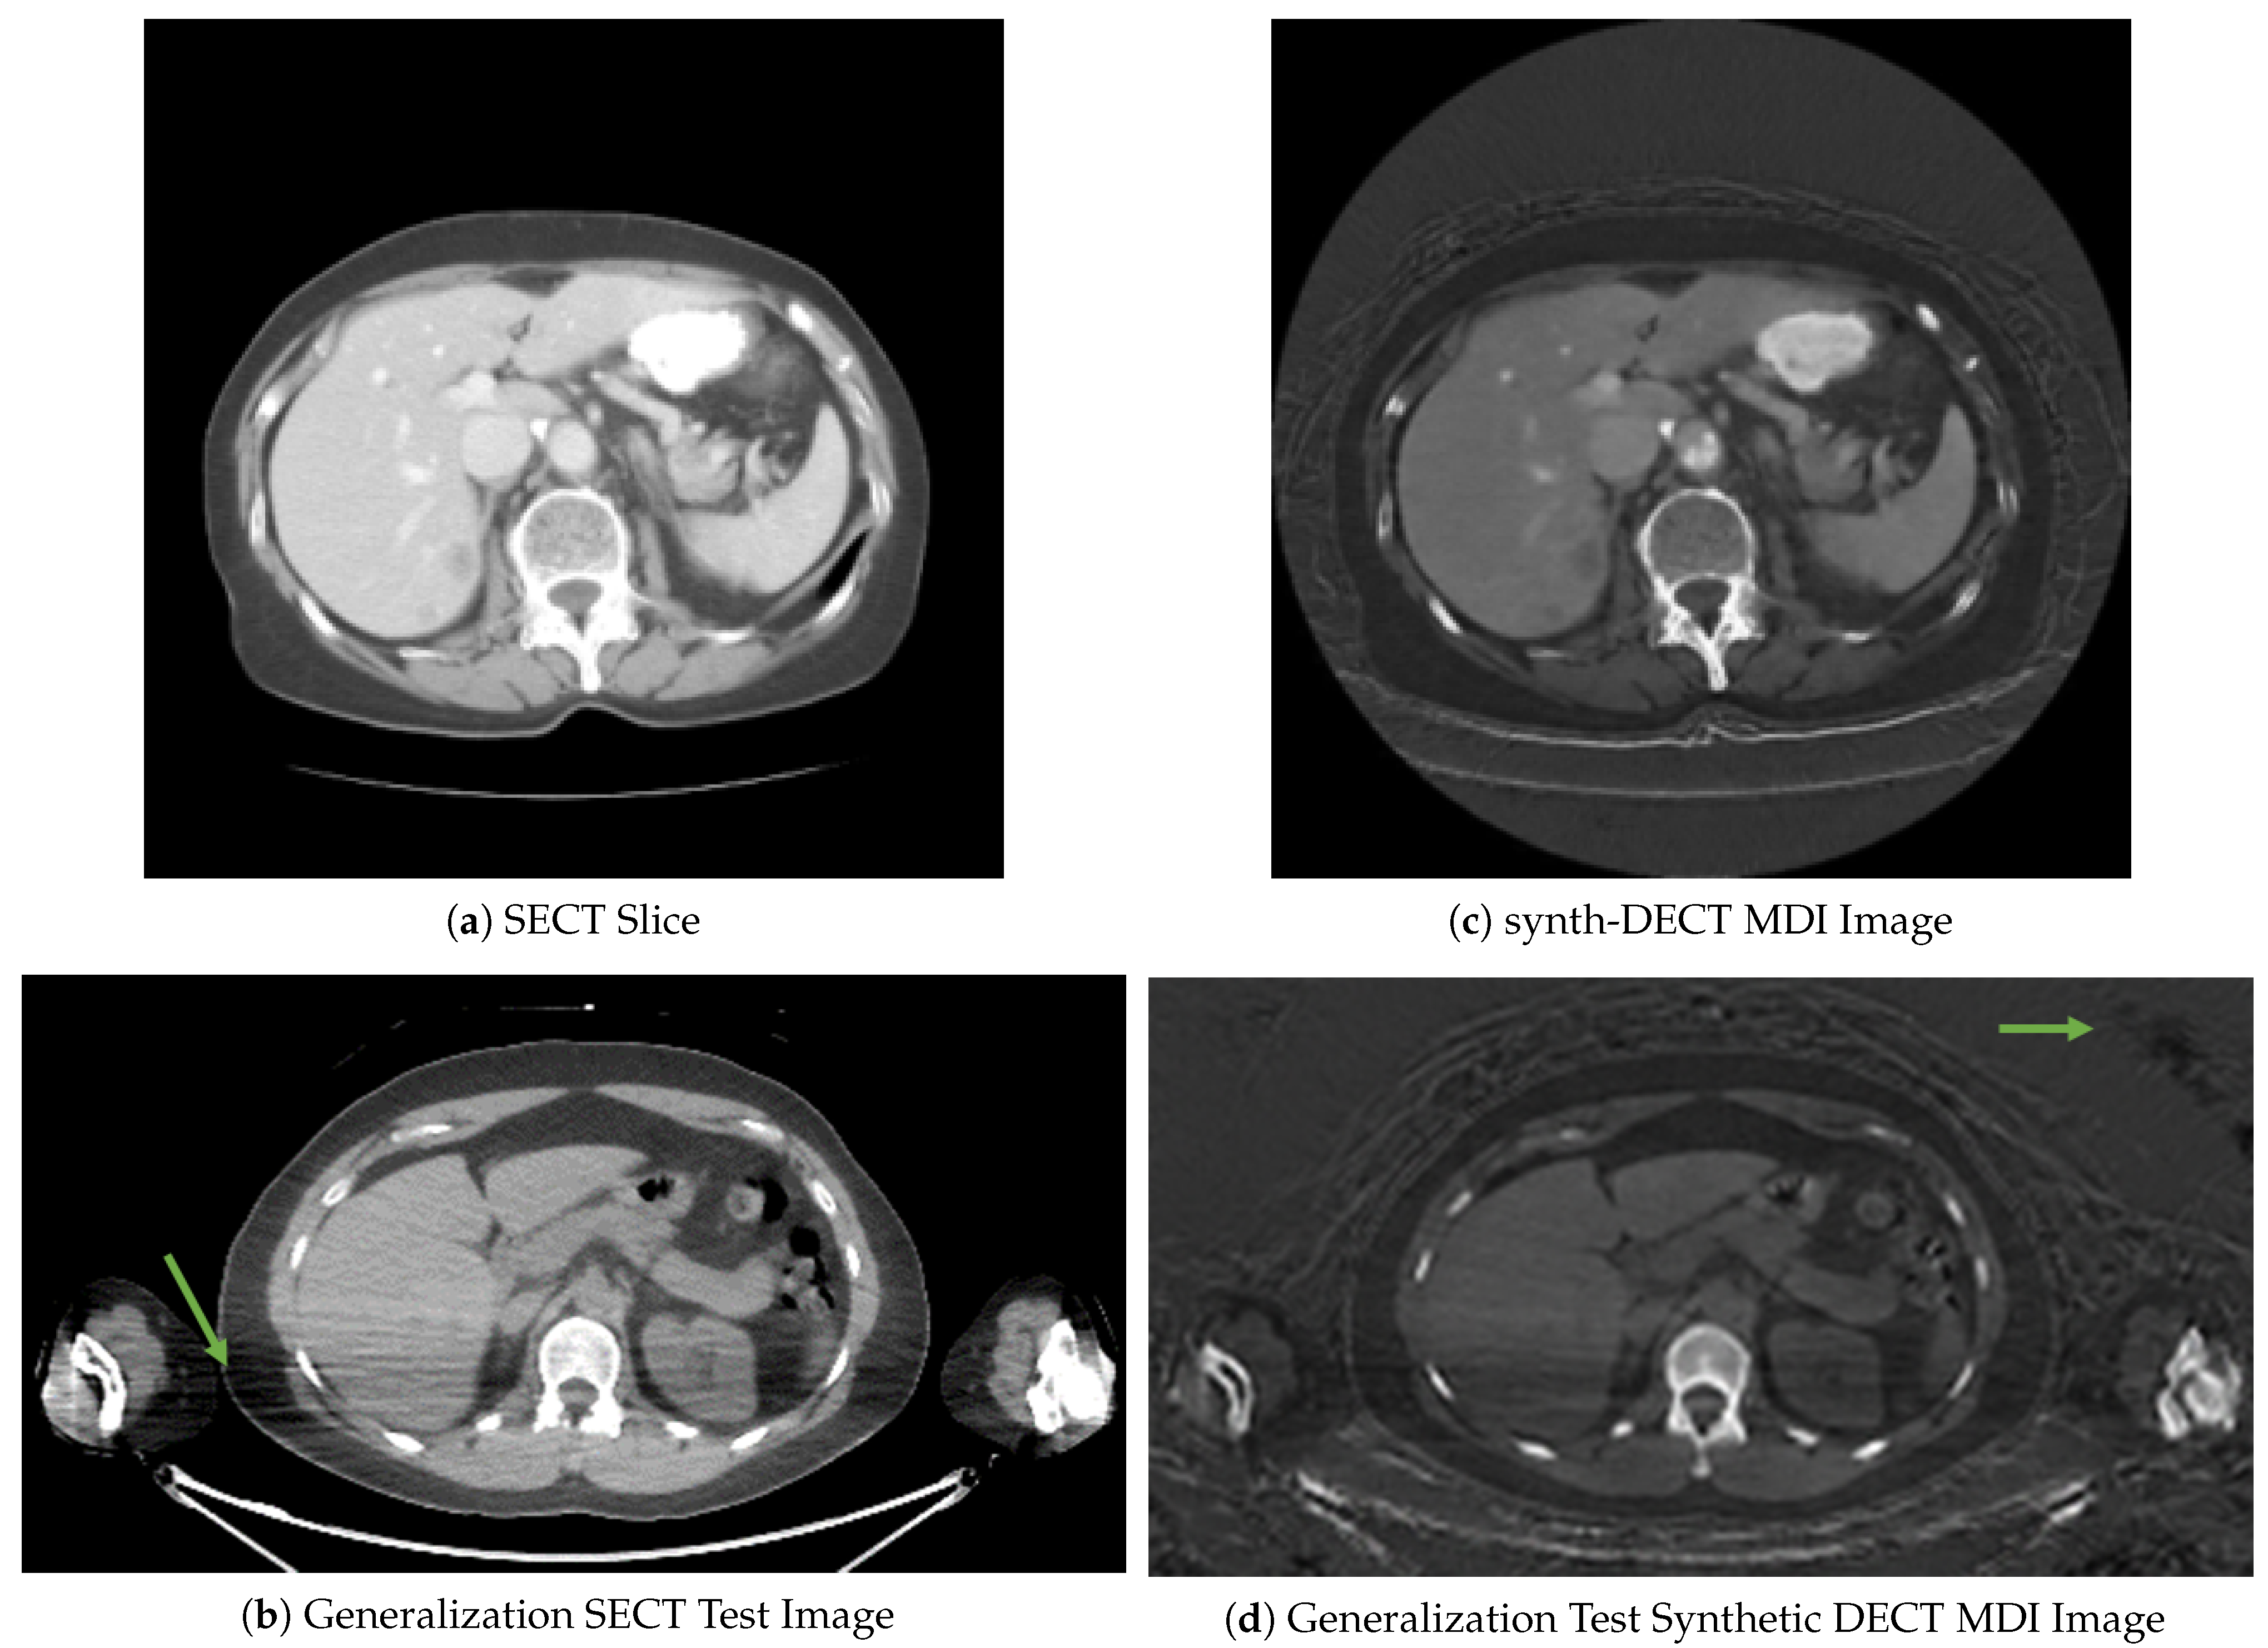

Figure 3. Example cross sectional axial slices from the test dataset used for Pix2Pix. (a) The original dual energy CT material density iodine (DECT MDI). (b) The synth-DECT MDI for the slice shown in (a). The global structural similarity index (SSIM) for the scan from which the slices were taken was computed to be 0.92. (c) This figure displays the local SSIM scores for each pixel of the slices in (a,b) as an image: The dark areas depict small values of the SSIM, which indicates a large difference between the original and synthetic image. The bright regions show large values of the SSIM or areas that were the most similar between the original and synthetic.

Across the nine test set scans, the average SSIM was computed as 0.94 ± 0.014 . Figure 3a,b shows an example cross-sectional axial slice from a single patient CT scan in the Pix2Pix test set. Subjectively, the original and synthetic slices in Figure 3a,b appear similar, but upon closer inspection, the base of the lung field pointed at in Figure 3a was blurred in the synthetic slice. Similar blurring in the lung field was observed across all test set scans. Figure 3c displays the local pixel level SSIM values computed between the slices shown in Figure 3a,b. The darker portions in Figure 3c point to air-filled cavities where the computed SSIM decreased. One reason for the low local SSIM within the air-filled cavities is that the effective attenuation of air within the lungs is neither similar to the two basis pairs, water or iodine, which were used to reconstruct the DECT image types. When the effective attenuation is unlike the two basis materials, a negative pixel value is assigned in the original DECT MDI scan.